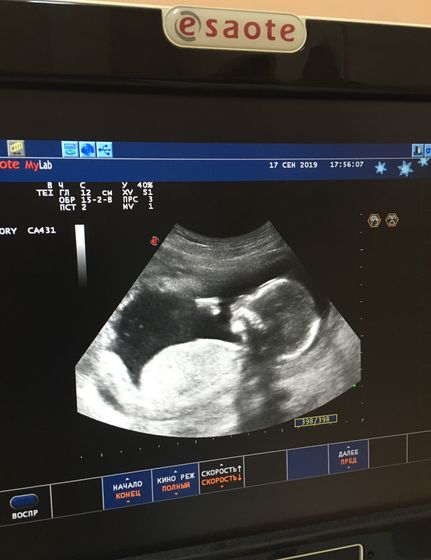

Сходила я сегодня на цервикометрию, шейка отличная длинная 3,9 см, зев закрыт, плацента чуть низко но потом поднимется))

?малыш прыгал, сосал пальчики и зевал, дали послушать сердечко и сказали пол...??у нас будет мальчик ????

Срок 16 недель и 2 дня)))